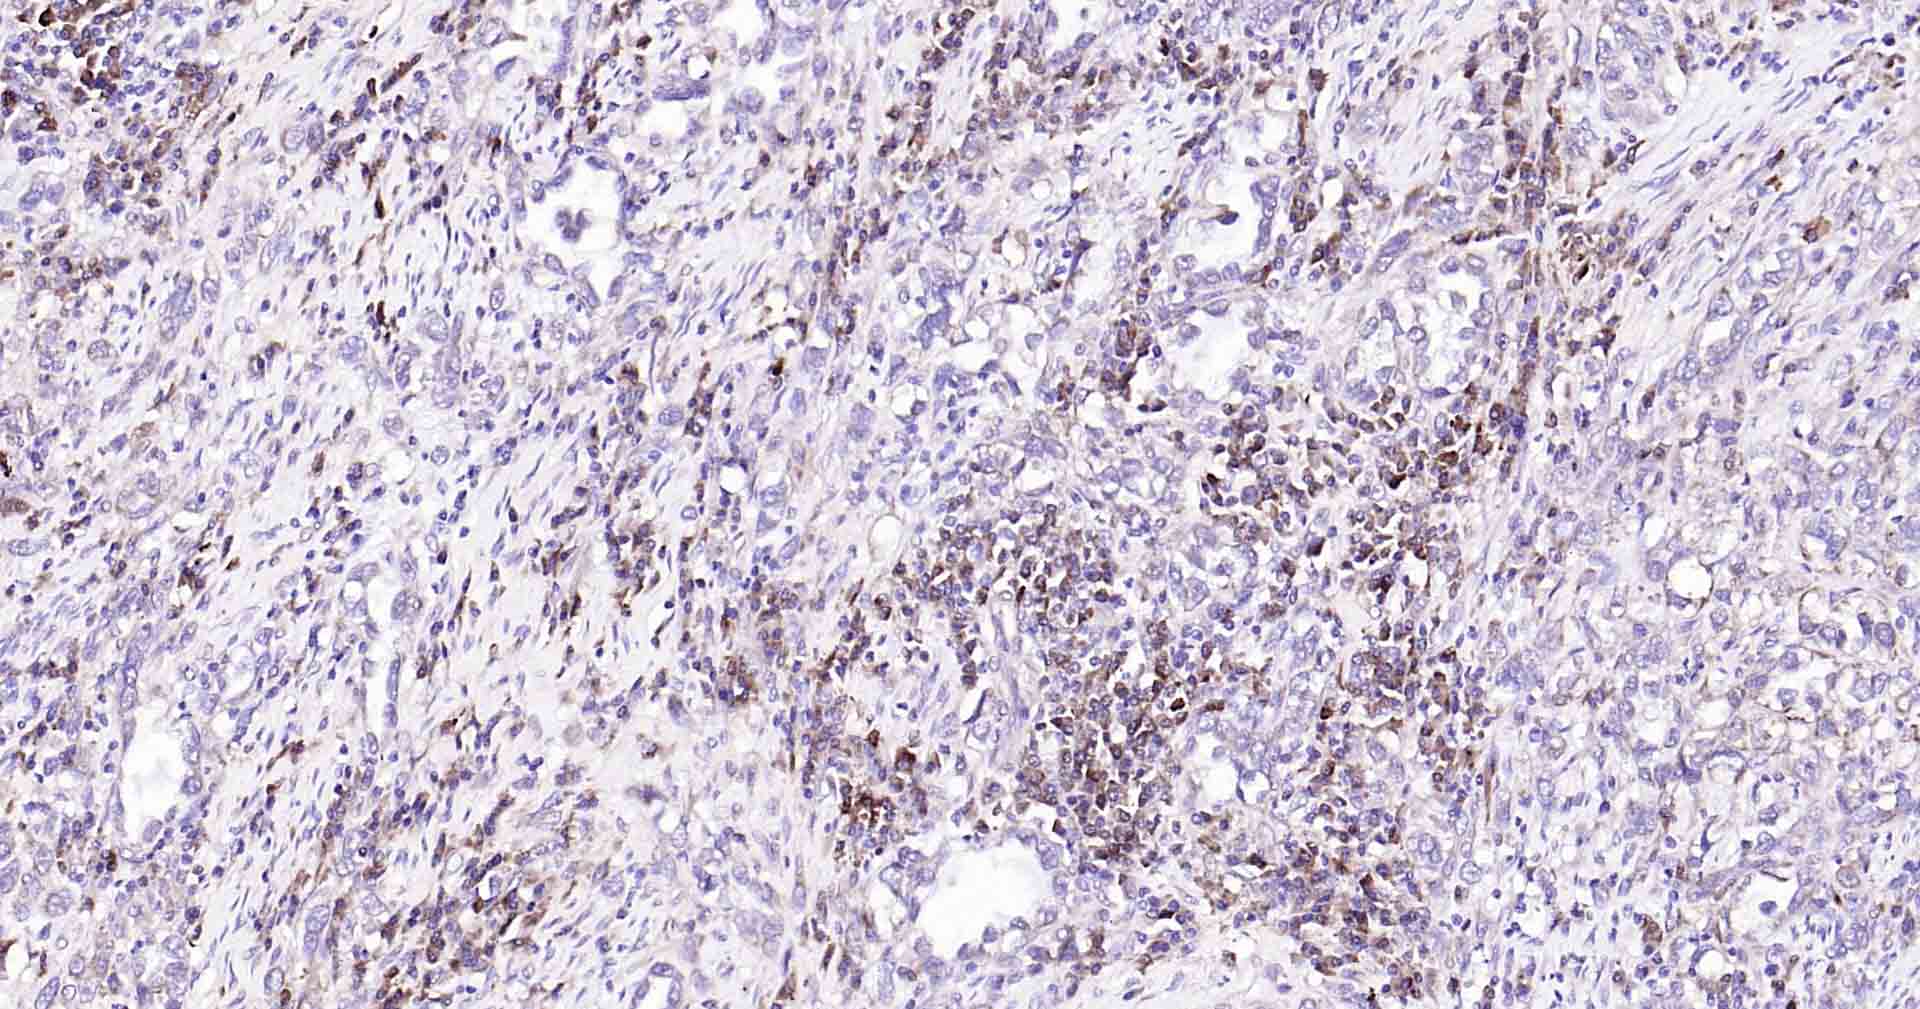

Paraformaldehyde-fixed, paraffin embedded Human Cervical Cancer; Antigen retrieval by boiling in sodium citrate buffer (pH6.0) for 15 min; Antibody incubation with Beclin 1 Monoclonal Antibody, Unconjugated(bsm-41365R) at 1:50 overnight at 4°C, followed by conjugation to the SP Kit (Rabbit, SP-0023) and DAB (C-0010) staining.